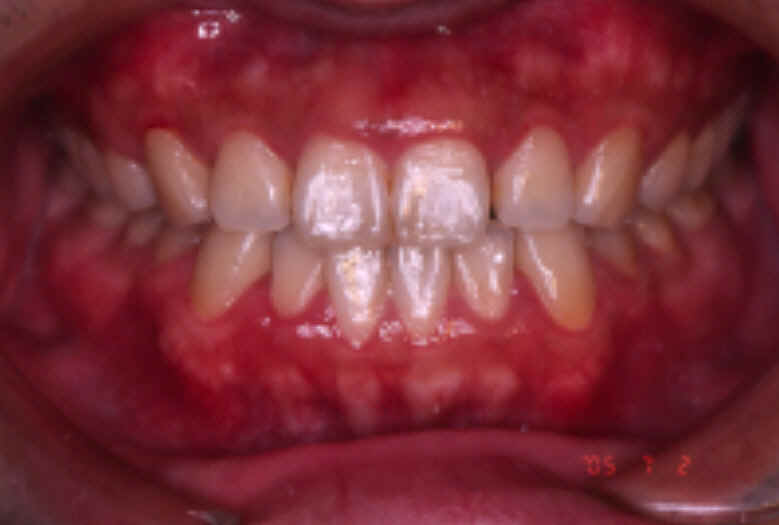

【治療後】

前歯の反対咬合が改善され

噛み合わせの適正な位置関係

が確立しました。